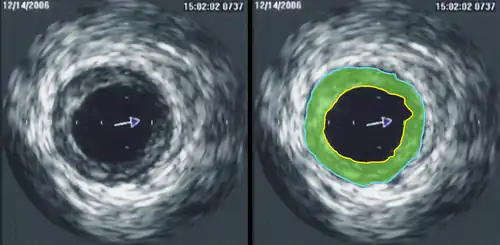

Intravascular ultrasound image of a coronary artery (left), with color-coding on the right, delineating the lumen (yellow), external elastic membrane (blue) and the atherosclerotic plaque burden (green). The percentage stenosis is defined as the area of the lumen (yellow) divided by the area of the external elastic membrane (blue) times 100. As the plaque burden increases, the lumen size will decrease and the degree of stenosis will increase.